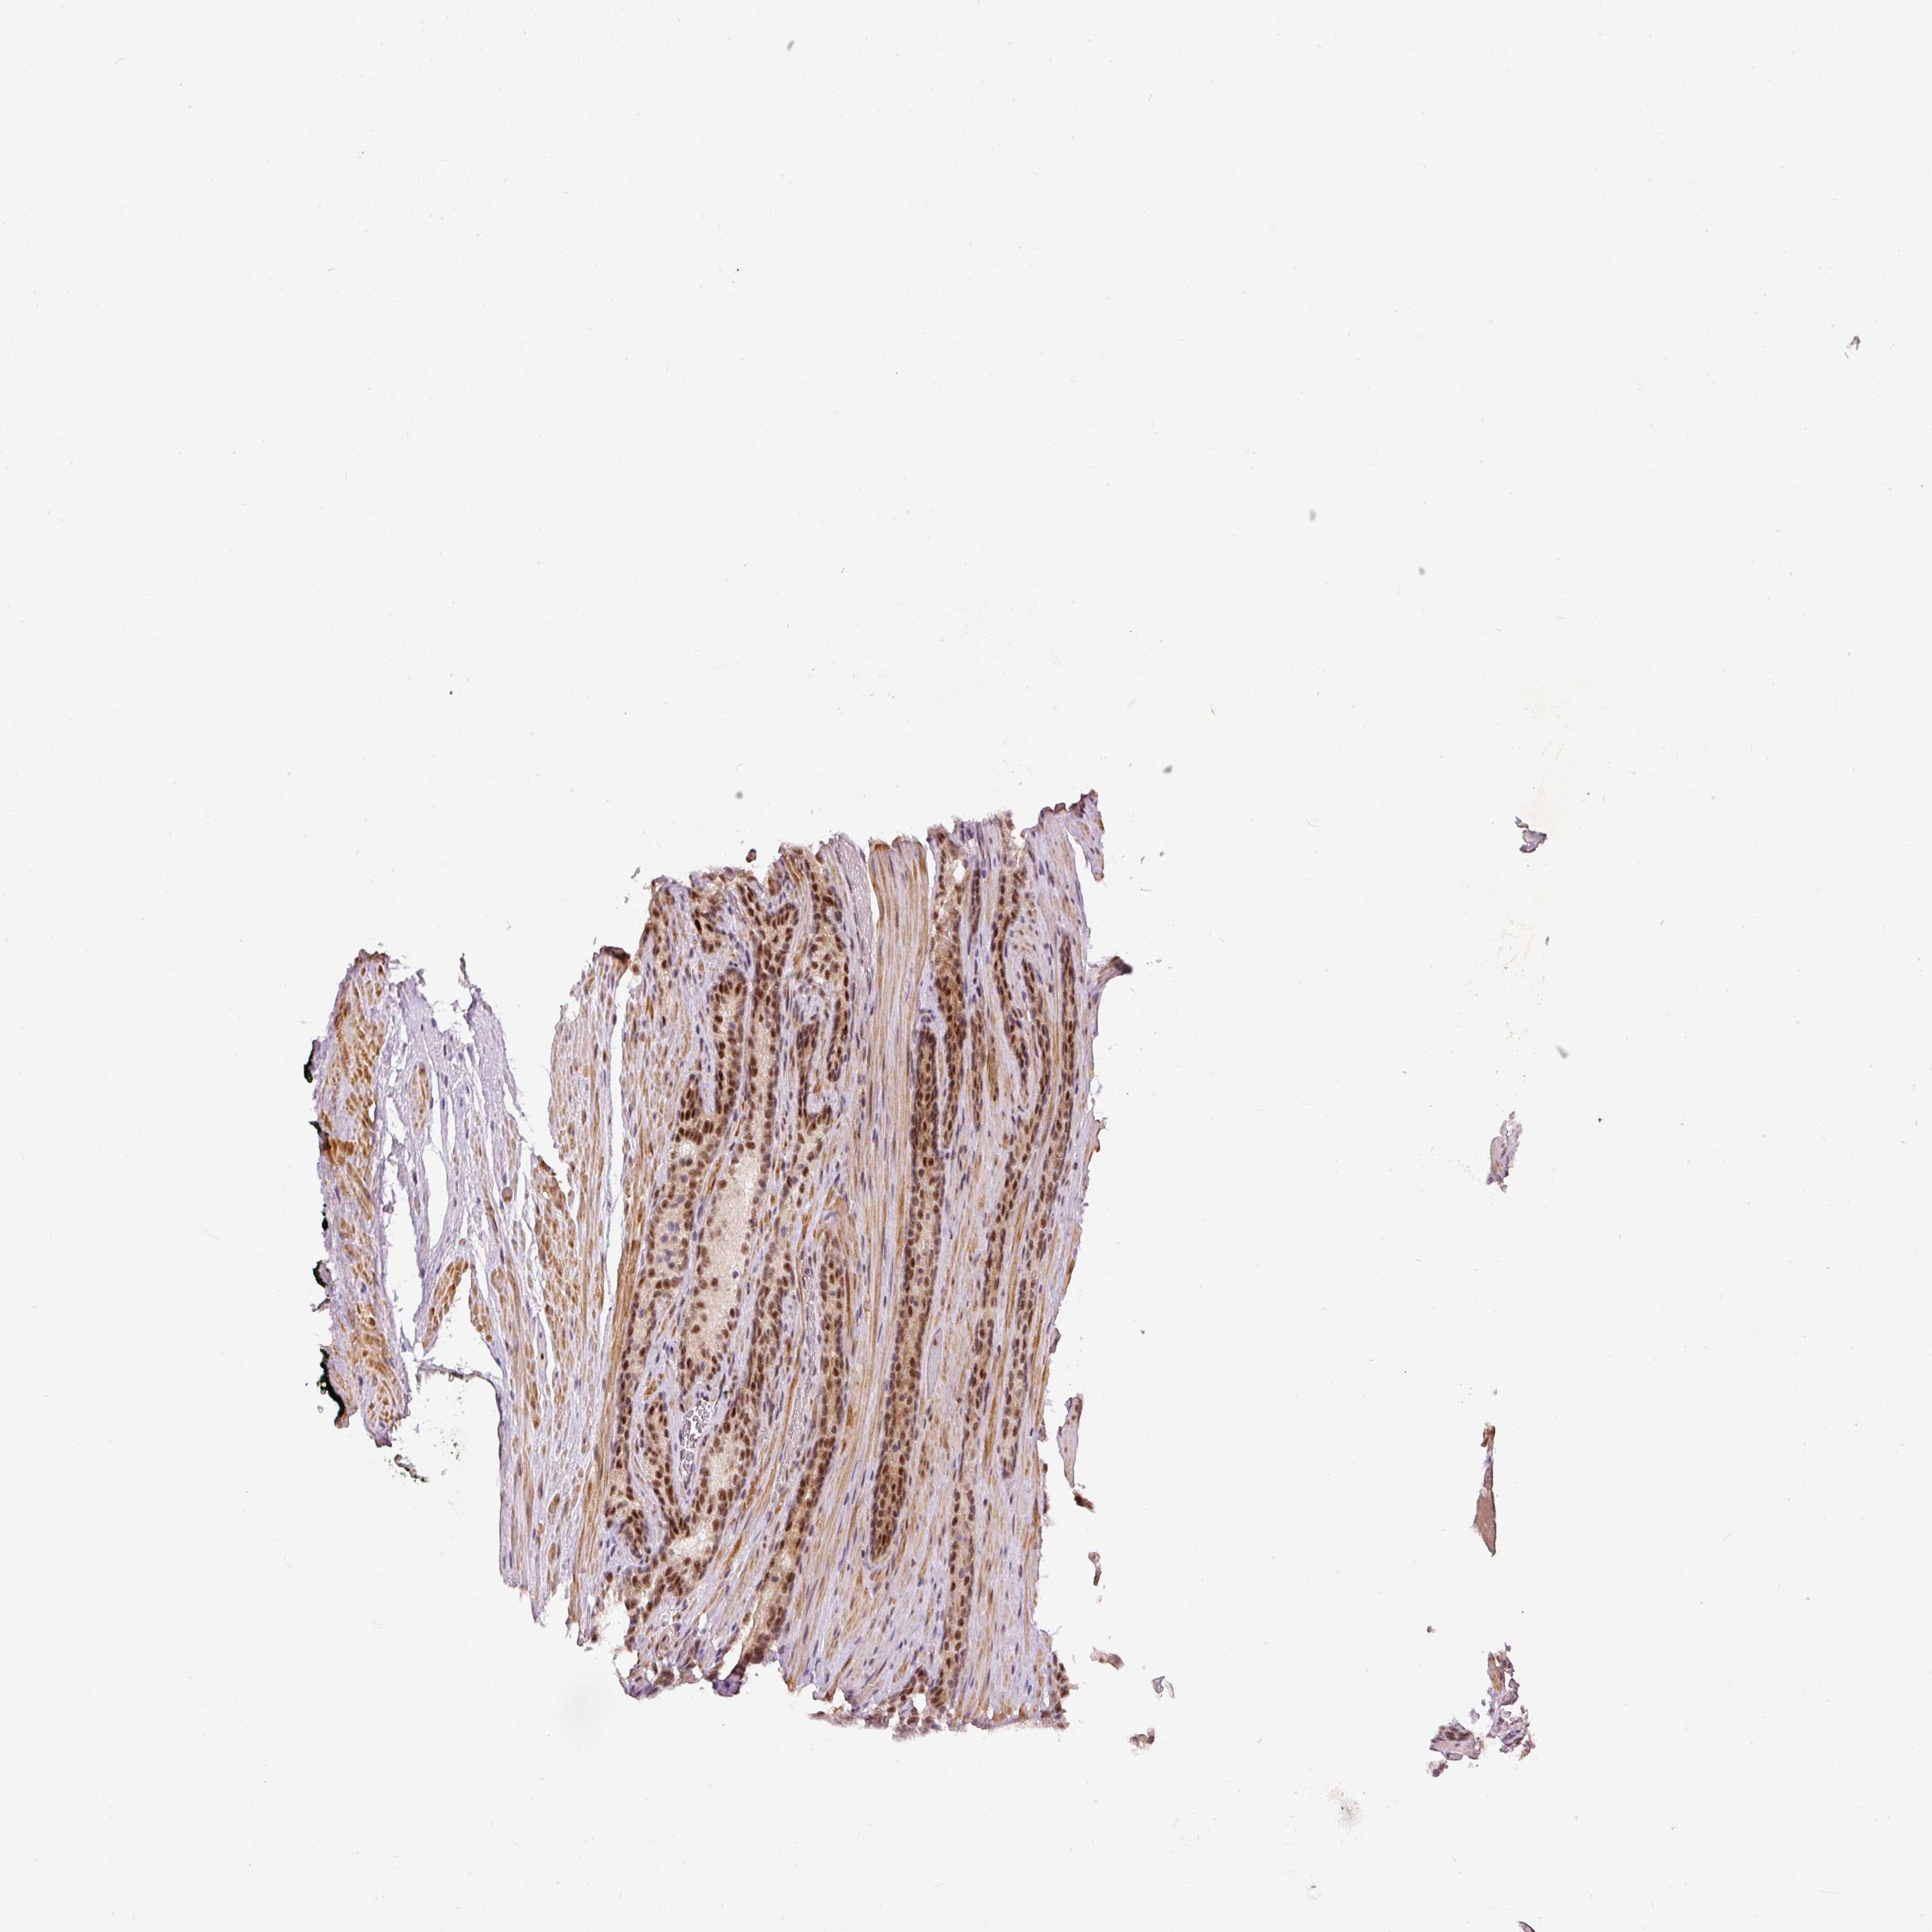

PROSTATE CANCER - Protein expressioni

A mouse-over function shows sample information and annotation data. Click on an image to view it in a full screen mode. Samples can be filtered based on level of antibody staining by selecting one or several of the following categories: high, medium, low and not detected. The assay and annotation is described here.

Note that samples used for immunohistochemistry by the Human Protein Atlas do not correspond to samples in the TCGA dataset.

Antibody stainingi

Antibody staining in the annotated cell types in the current human tissue is reported as not detected, low, medium, or high, based on conventional immunohistochemistry profiling in selected tissues. This score is based on the combination of the staining intensity and fraction of stained cells.

Each image is clickable and will lead to virtual microscopy that enables deeper exploration of all samples and also displays staining intensity scores, fraction scores and subcellular localization as well as patient and tissue information for each sample.

Antibody HPA052953

Staining

High

Medium

Low

Not detected

Intensity

Strong

Moderate

Weak

Negative

Quantity

>75%

75%-25%

<25%

None

Location

Nuclear

Cytoplasmic/membranous

Cytoplasmic/membranous,nuclear

Adenocarcinoma, NOS

Adenocarcinoma, High grade

Adenocarcinoma, Low grade